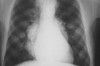

Infection of the respiratory tract can be defined as upper or lower respiratory infection. Most people are getting confused on how to differentiate these two contagious diseases. In today’s post though, we’ll be dealing mainly with the upper respiratory infection (URI), however we’ll also touch a little about the lower infection. To start off, a […]